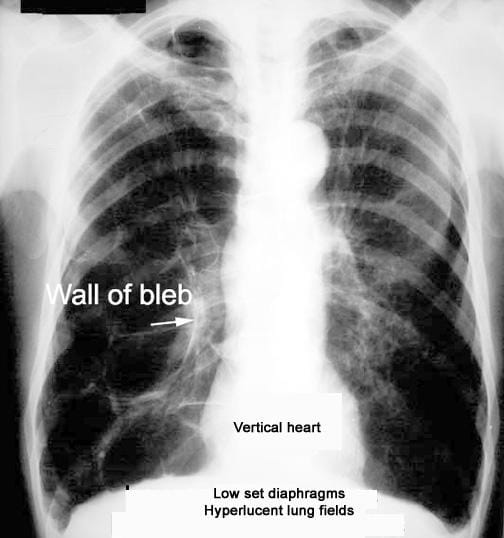

• X-rays may show some changes in the lungs caused by emphysema; however, a CT scan gives much greater detail of changes in your lungs than a chest X-ray does.